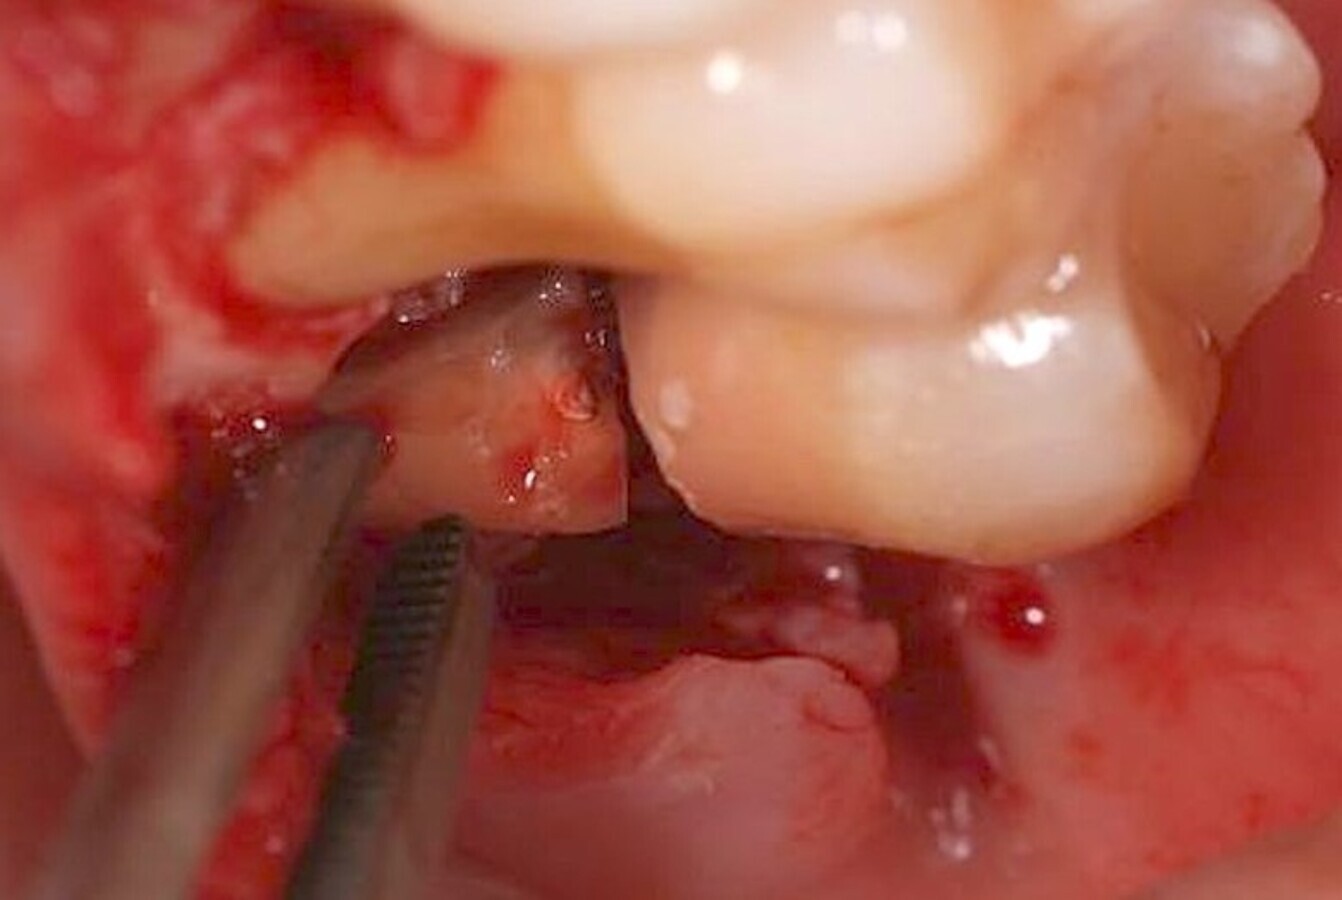

Algunos láseres como los de erbio, y en mi día a día en concreto el de Er,Cr:YSGG (Waterlase), permiten realizar un corte óseo quirúrgico muy preciso (Figuras 9-13), que transmite un daño térmico mínimo a los tejidos adyacentes9.

El láser Er,Cr:YSGG de alta potencia permite realizar cortes óseos quirúrgicos muy precisos (ver Figuras 9-13).

Figura 9.

Figura 10.

Figura 11.

Figura 12.

Figura 13. Las figuras 9-13 permiten observar un corte óseo quirúrgico muy preciso realizado con láser de erbio que produce un daño térmico mínimo en los tejidos adyacentes.